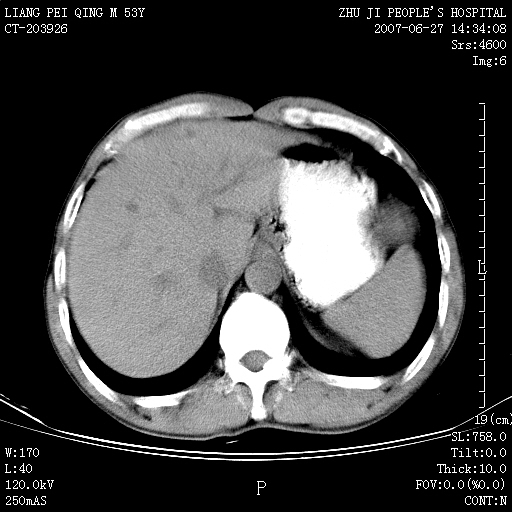

以下是引用余辉在2007-6-27 18:46:00的发言:[br]病灶多发,内可见大片状低密度区,病灶病灶等密度区轻度强化,动脉期后期病灶低密度区与高密度区对度增加,考虑1淋巴瘤2转移瘤3血管内皮细胞瘤(不知有否静脉期及延迟期扫描)

以下是引用zzzzhhhhaaaannnn在2007-6-27 20:44:00的发言:[br]脾脏 肋骨转移可能性大,下腔静脉内有癌栓

以下是引用狙击手在2007-6-28 10:35:00的发言:[br]1:定位:来源于脾脏。2:强化:强化,但不均匀。3:下腔静脉癌栓?下腔静脉充填不均匀与增强时间有关,延时即可明确。4:肋骨破坏?看起来并不确切。综上考虑几个最常见诊断:1;淋巴管瘤;2;血管内皮肉瘤(高度恶性,早期即可转移,常见肝,肺,骨)3;转移瘤(无特征性,只有肝或其它腹腔脏器有类似病变时,才可提示之)